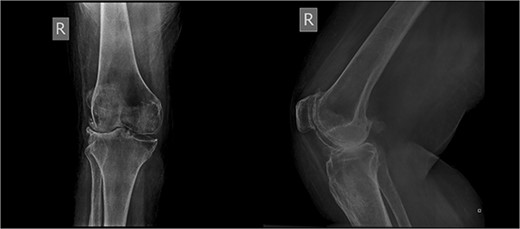

The patient underwent a medial-pivot design TKA (Evolution Medial-Pivot Knee System, Microport, China). Intraoperatively, a full ROM was achieved only after extensive soft tissue and bone releases. The extension gap was limited by significant hamstring spasticity, and a proper extension gap was attained after additional anterior femoral cut. Early postoperative recovery was uneventful (Fig. 2). On the third postoperative day, the patient complained of severe knee pain accompanied by excessive swelling during kinesiotherapy. Clinical examination showed a posterior sag sign at 30° of flexion (Fig. 3). No signs of neurovascular deficit were obvious. A knee X-ray revealed posterior TKA dislocation and a small, non-displaced femoral fracture (Fig. 4). The tibial component was reducible, but redislocation occurred with the knee extended over 90°, indicative of severe instability. Laboratory investigations, including erythrocyte sedimentation rate and C-reactive protein, were normal. A knee arthrocentesis was performed with no substantial findings. Two botulinum toxin injections (200 IU) to the hamstrings were performed without improvement. Local muscle hypertonia was evaluated through a neurological examination and a brain computed tomography scan, with no remarkable findings. The patient’s history included intramedullary nailing of the right femur due to an intertrochanteric fracture 8 months before the TKA.